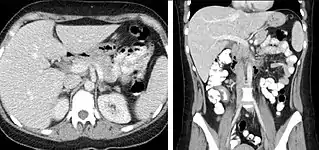

When evaluating hepatic masses, it can be advantageous to have both late arterial and portal venous phase images (biphasic imaging, figure 4) since some tumors enhance briskly during the arterial phase (hepatocellular carcinoma, hepatic adenoma, follicular nodular hyperplasia (FNH), and hypervascular metastasis), but may be occult or difficult to characterize on portal venous phase imaging alone (figure 6). However, it should be stressed that the addition of late arterial phase images is only indicated if one of these tumors is suspected, or if there is a need for further characterization of a hepatic mass, since the large majority of patients will not benefit from the addition of this phase. In addition, if there is a need to definitively characterize a hepatic mass, MRI is generally more sensitive and specific, with no associated radiation dose.